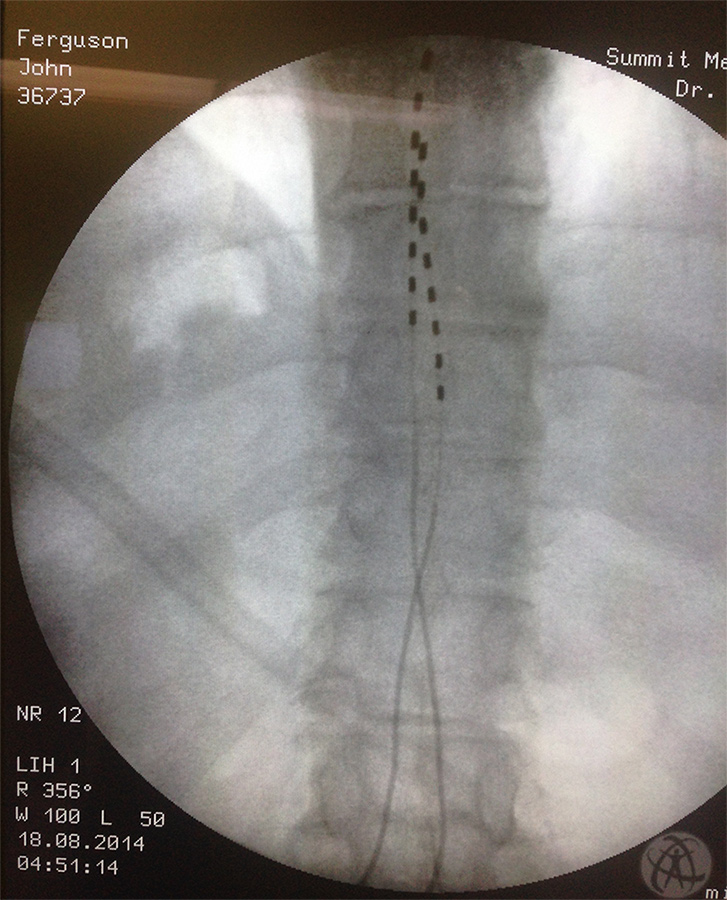

Like you, I know back pain well. I have a dead disc between my L4 and L5 vertebrae, as well as a bone spur that intrudes into my spinal nerve cluster, so I have suffered with shooting sciatica and back pain in various locations for many years - it really limits my mobility and what I can do. I can handle the pain fairly well, but what gets me is that I am limited when playing with my young 6 year old daughter. Of course insurance doesn't pay for disc replacement surgery and I refuse to get my spine fused, but C'est la vie... But as bad as back pain can be, just count your blessings that you don't have a kidney stone - now that's pain!